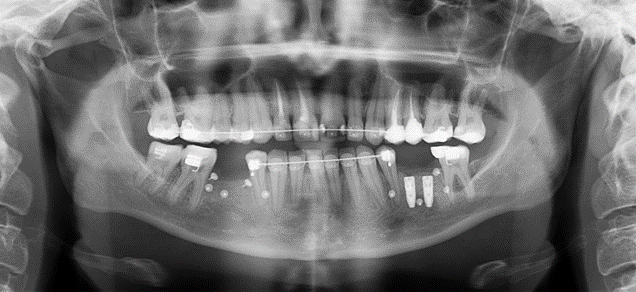

Весь рот в гвоздиках

Это пины. Тут ещё брекеты, неметаллические. Эстетические выгоднее. Вместо пятого и шестого зубов. Перемещение седьмого зуба — ортодонтию сначала. Моляры отодвигались назад.

А вот аугментация кости. Не та, которая в компьютерных играх со всякими наночипами, а просто наращивание кости экзогенной. Точнее, щебёнка из кости бычка (откуда выжгли весь белок) в качестве стройматериала и фибрин из крови пациента. Получается пластичная масса, которую помещают под мембрану. Мембрану прибивают пинами — вот этими маленькими гвоздиками типа мебельных.

Вот ещё пример:

Здесь объём побольше, просто графт не подходит. Установлен костный блок из нижней челюсти.

Треугольник сбоку — это лунка переднего корня шестого зуба. Костный блок немного меньше ложа, дальше всё нормально заполнится костной тканью. Естественно, выполнение такой работы невозможно без томограммы.